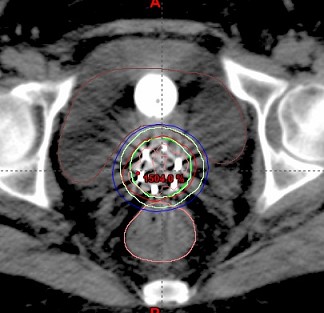

图2 后装插植植入治疗妇科肿瘤病例